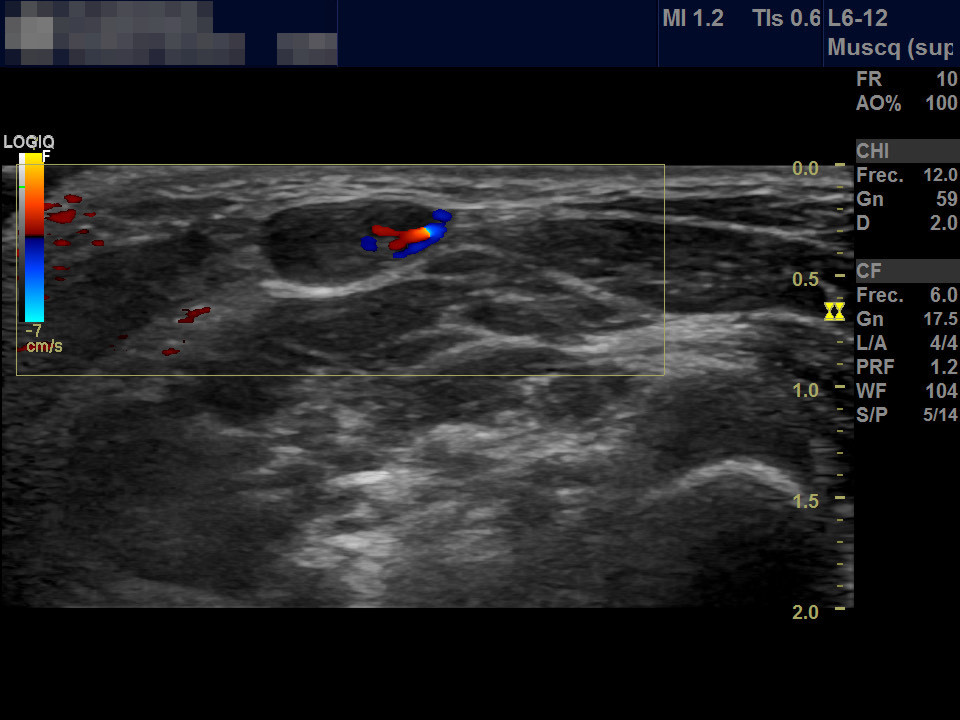

Niño de 7 años que acude a consulta de Atención Primaria por aparición de tumoración cervical de 2 días de evolución. A la exploración en la región lateral cervical posterior al esternocleidomastoideo se aprecia una tumoración móvil no adherida de consistencia blanda de aproximadamente 1 cm de diámetro sin cambios superficiales acompañantes. No presenta otra clínica sistémica asociada. Antecedentes personales y familiares sin interés. No habían observado similar lesión en otras ocasiones. Realizamos ecografía simple (Figura 1) y ecografía Doppler de la lesión (Figura 2).

Figura 2. Detalle mediante la técnica de Doppler color con la captación a nivel central de vascularización.